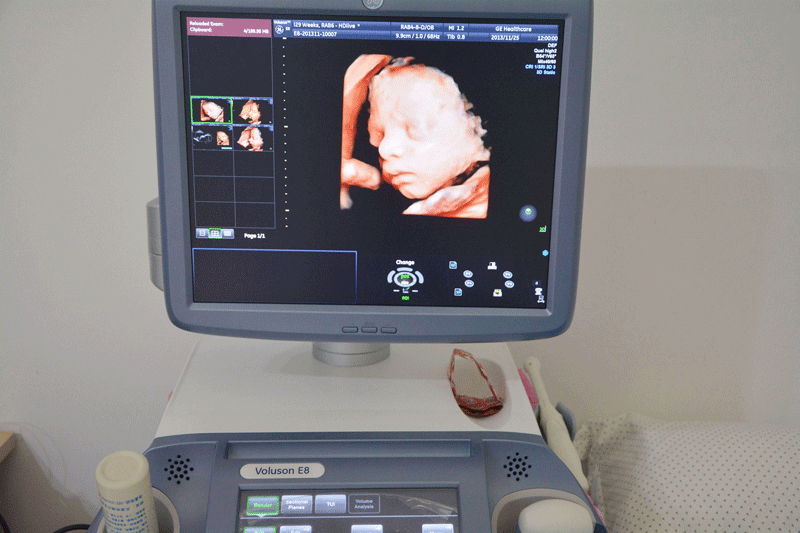

三维彩超,即彩色多普勒超声检查的一种,检查图像呈土黄色,通过多普勒超声仪器发出超声波,对体内各项器官进行成像。三维即其图像是立体的,可以更直观的看到器官的形态,及时发现病变并进行治疗。三维彩超常用于产检,用来判断胎儿的生长发育的情况或是否出现畸形等。

产检中,三维彩超通过测量子宫纵径、子宫体横径、子宫前后径这三条径线来观察胎儿是否正常。以及通过三维立体的成像,可以清晰的显示出胎儿各个内脏器官,以及面部器官、四肢的情况,来简单的判断胎儿是否存在畸形,包括胎儿是否患有先天性心脏病也是能够检查出来的。

24周的胎儿,其身体结构的生长发育已经很完善了,且胎儿大小也很合适,这时候做三维彩超可以很直观的看到胎儿的五官四肢、以及内脏器官,还能了解胎儿双顶径、头围、腹围、股骨长等发育情况。

2、清晰度不同

三维和四维并不是彩色图片,只是和黑白色有差异,二者呈现的都是土黄色的画面。但三维的成像是静态的,是一张图片,而四维彩超则是动态的,像一张动图一样,并且有的医院会允许刻成光盘带回家收藏起来。